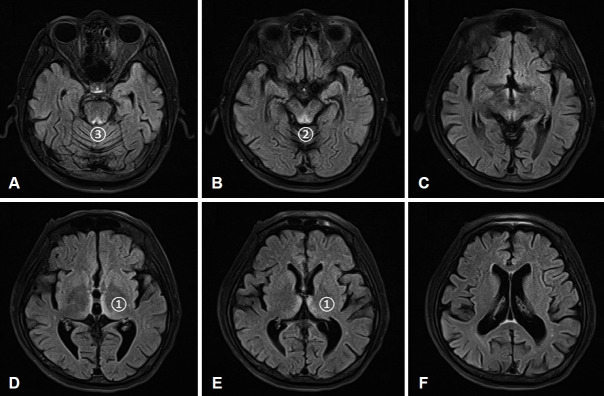

韦尼克脑病,又称硫胺素缺乏症,其特征是三种症状:眼麻痹、共济失调和精神错乱。然而,根据病变影响的区域,可能会出现其他症状。虽然多发性颅神经病变是可能的,但突发性双侧听力丧失在罕见的情况下被描述为韦尼克脑病的第一表现。在这里,我们提出一个病例报告,详细介绍了一个被诊断为韦尼克脑病的患者的临床经验,其最初的表现包括突发性双侧耳聋。患者是一名57岁的酗酒男性,他被成功诊断为韦尼克脑病,在大剂量静脉注射硫胺素治疗后,他的听力有所改善。我们的病例研究结果和文献综述表明,视频结果和抑制头部脉冲试验可用于评估韦尼克脑病。

Wernicke encephalopathy, also known as thiamine deficiency, is characterized by a triad of symptoms: ophthalmoplegia, ataxia, and confusion. However, additional symptoms may manifest depending on the area affected by the lesion. Although multiple cranial neuropathies are possible, sudden onset bilateral hearing loss has been described in rare situations as the first manifestation of Wernicke encephalopathy. Here, we present a case report detailing the clinical experience of a patient diagnosed with Wernicke encephalopathy, whose initial presentation included sudden bilateral deafness. The patient was a 57-year-old man with alcoholism who was successfully diagnosed with Wernicke encephalopathy, and his hearing improved after high-dose intravenous thiamine therapy. Our case study results and a literature review indicate that video findings and suppression head impulse tests can be used to evaluate Wernicke encephalopathy.